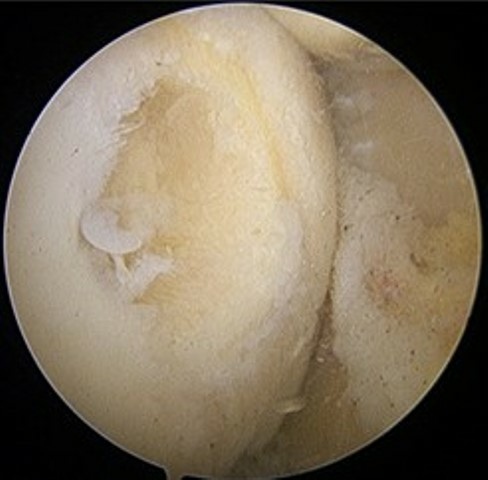

方啟榮醫師指出,隨著再生醫學與生物材料技術的進步,近年來出現了一次性微創軟骨修復手術,利用單次的關節鏡手術在受損區域同時進行清創與修補,透過特殊的載體及酵素作用,幫助關節內自行生成新軟骨。整個手術過程僅需小小的關節鏡切口,不僅減少手術次數,也降低感染風險與疼痛感。

方啟榮醫師表示,更令人振奮的是,術後兩年的影像追蹤顯示她的軟骨組織在缺損部位已再生並覆蓋良好,臨床上不僅疼痛消失,關節穩定度與活動度也大幅改善。對一位年輕、仍需長期使用膝蓋的女性來說,這樣的結果不只是醫學上的成功,更是生活品質的重生。